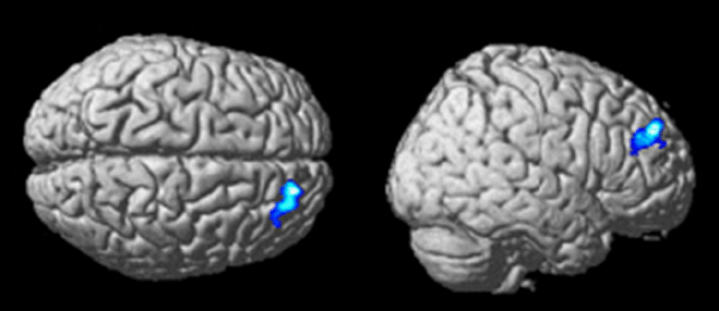

В рискованном поведении участвуют две зоны мозга. Первая — островковая доля, которая в числе прочего отвечает за сострадание, обработку информации о социальных нормах и непринятие рисков. Вторая — прилежащее ядро. Оно входит в ту самую Систему 1, реагирует на всё приятное, рассчитывает ценность награды и толкает на риск.

Профессор Стэнфордского университета Брайан Кнутсон выяснил, что если прилежащее ядро возбуждается от обещания удовольствия, то оно определяет нашу склонность к риску. В исследовании Кнутсона мужчины видели на экране эротические фотографии, а потом принимали рискованные финансовые решения. На снимках ФМРТ было видно: когда их мозг ожидал фотографию, прилежащее ядро становилось активнее и толкало испытуемого на более смелые решения.

Всегда, когда перед вами стоит неочевидное решение, островковая доля и прилежащее ядро конкурируют друг с другом. Побеждает тот, чей импульс — страх потери или ценность награды — оказался сильнее. Проверьте это на себе прямо сейчас. Посмотрите, как меняется ваша реакция в зависимости от формулировки:

Но конечно, в этом примере выгоду легко вычислить. В дело вступила Система 2 — дорсолатеральная префронтальная кора, которая обработала информацию и «перекричала» неосознанные импульсы. Вот что она вам сказала: «Да это одинаковые варианты! Что за развод?»